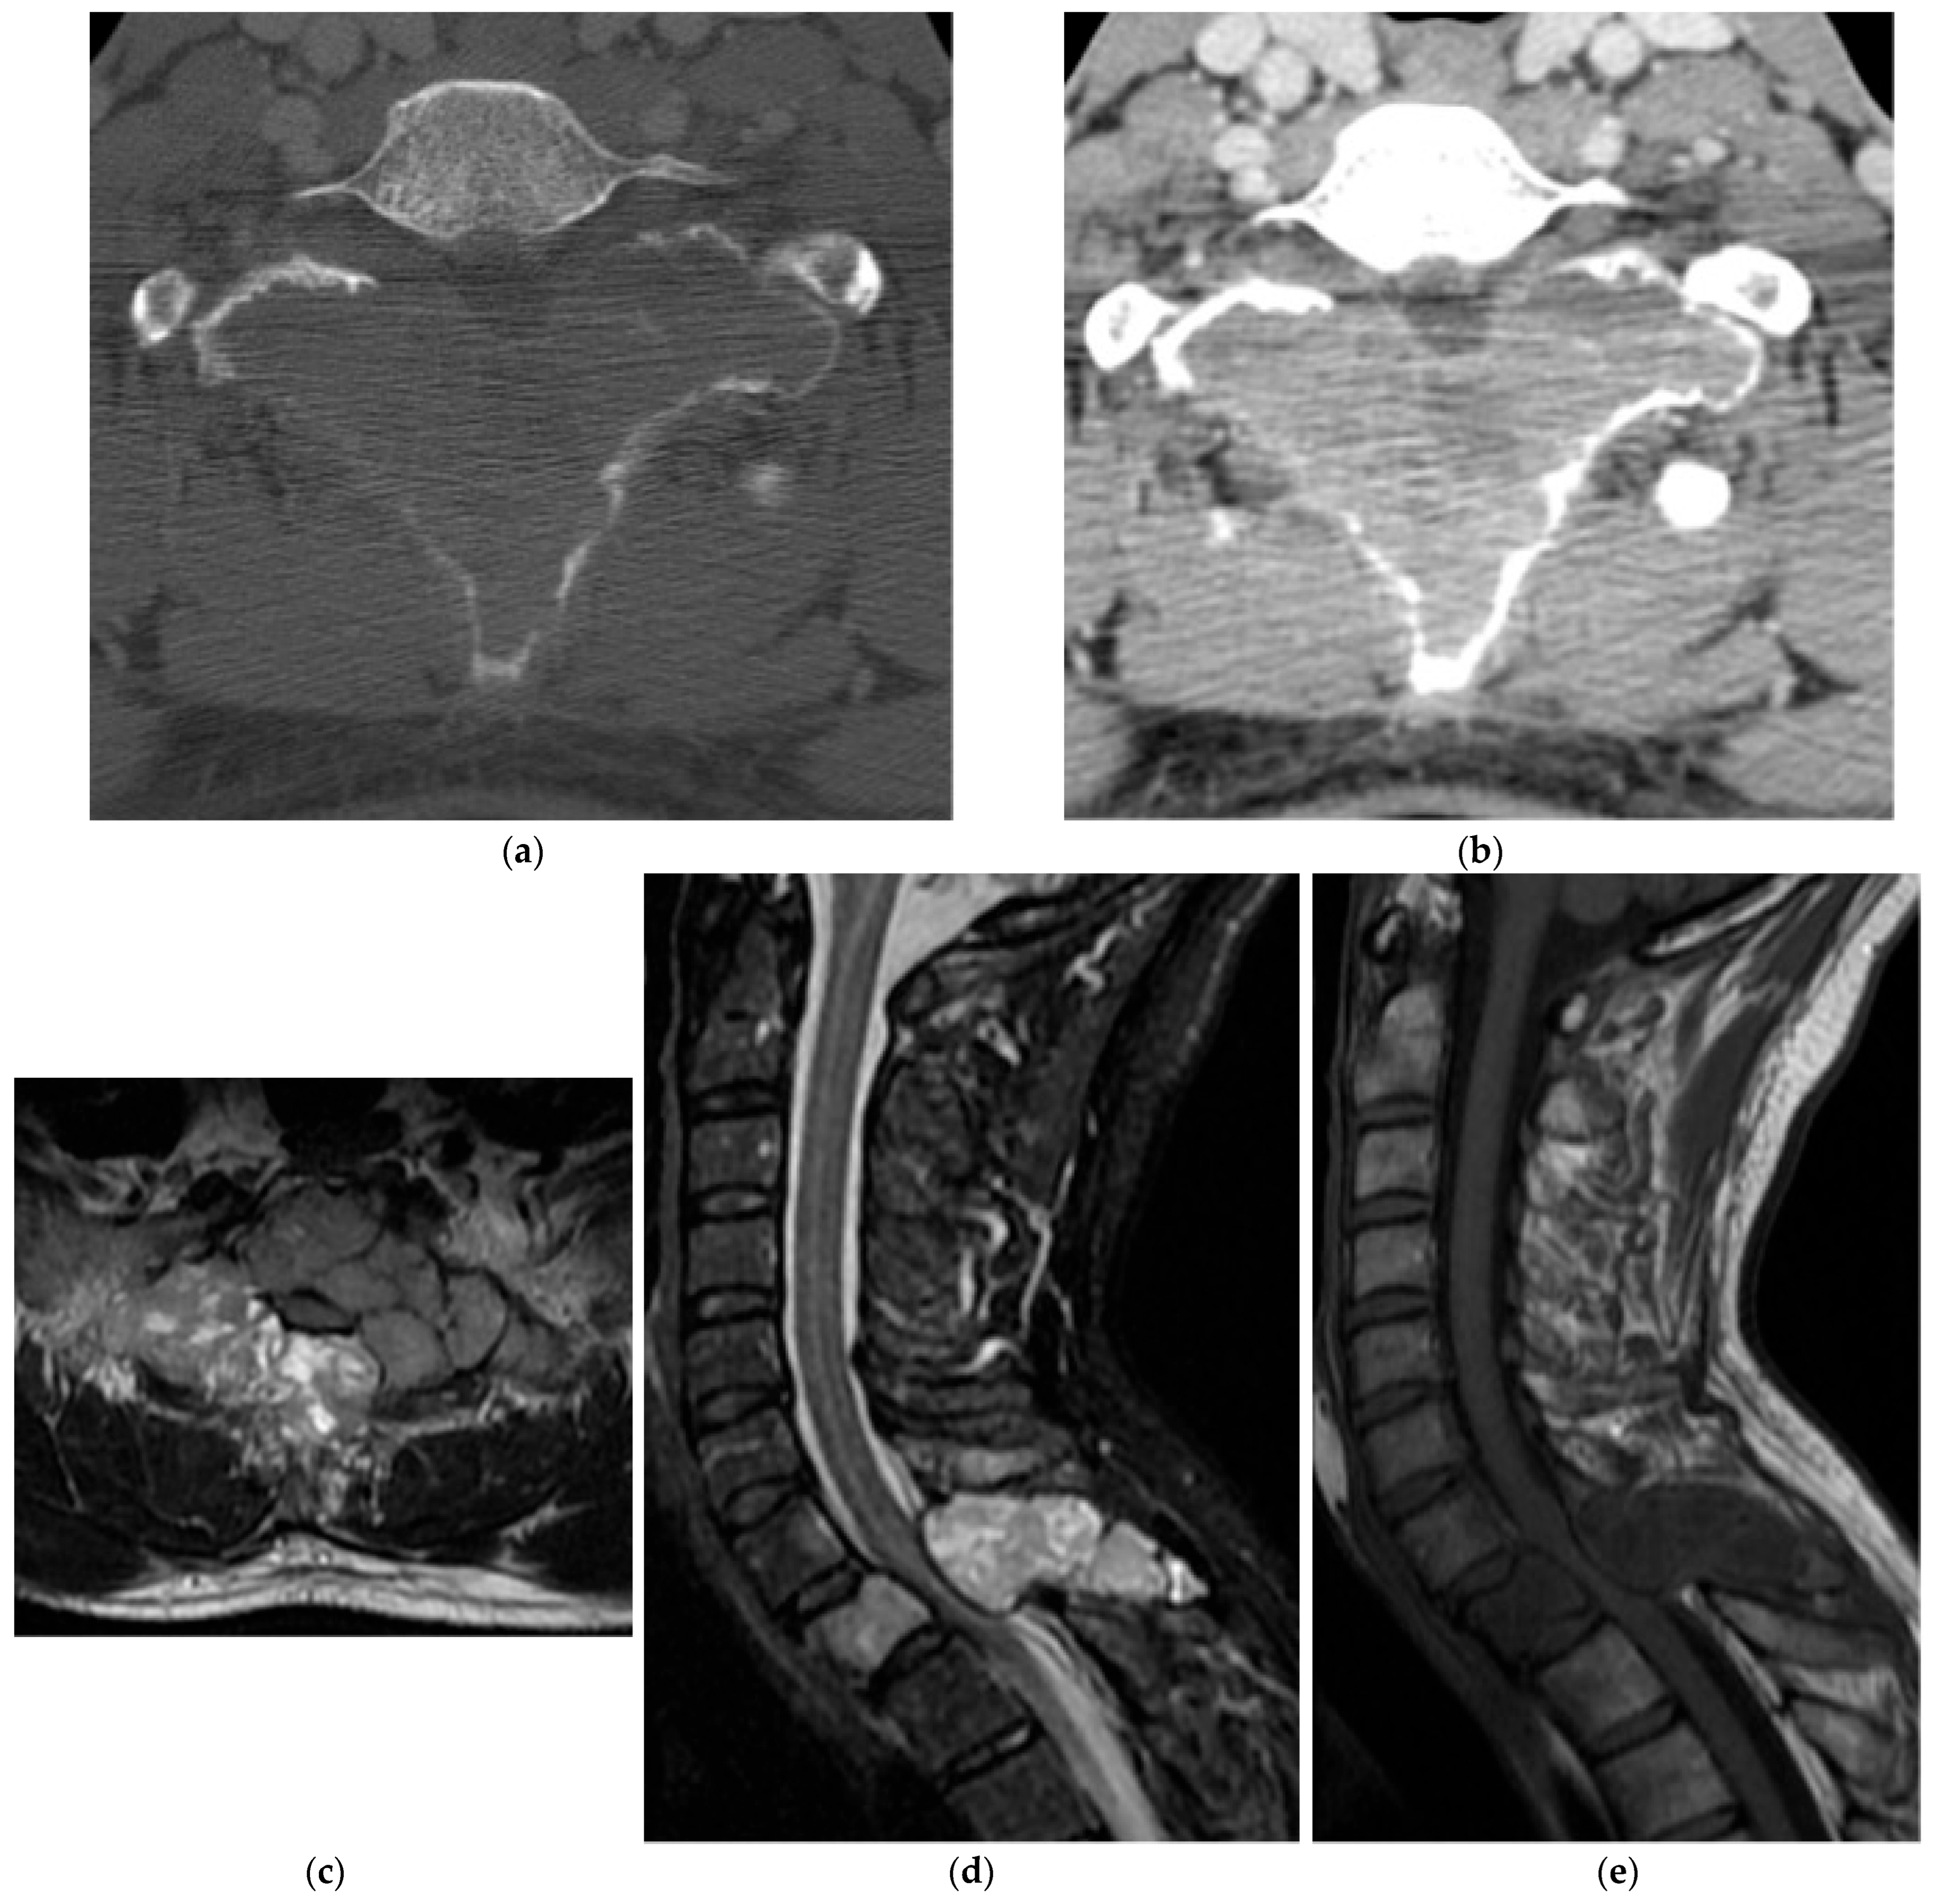

2.3.2. Chordoma